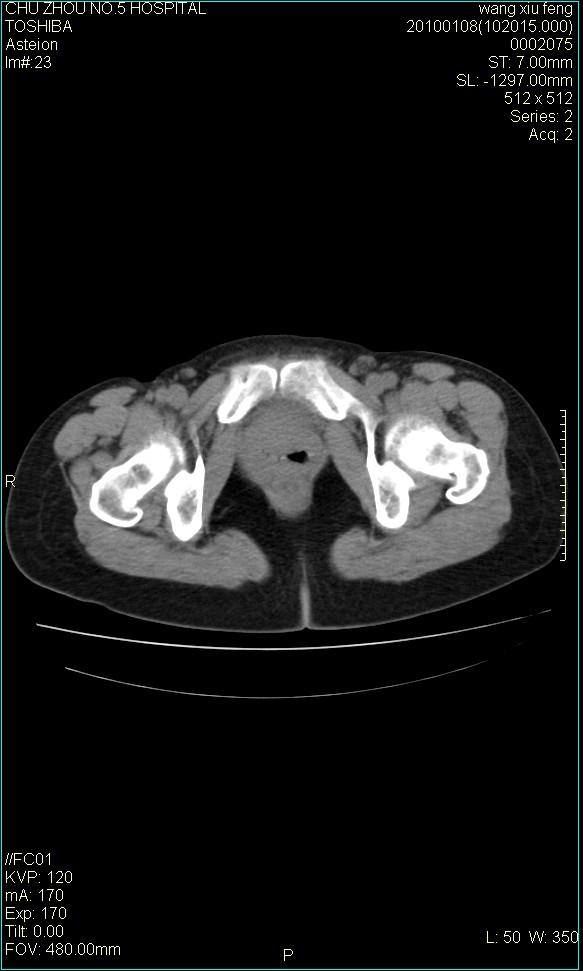

f-41,左乳腺ca术后4年,b超示:子宫右上方囊性包块约5.5*3.4cm,前日行胸部ct平扫未见明显异常。

考虑右侧卵巢囊腺瘤?

右侧卵巢囊肿或小囊腺瘤。

考虑右侧卵巢囊腺瘤?建议增强!

考虑右侧卵巢囊腺瘤。

考虑右侧卵巢囊性占位性病变(囊肿?囊腺瘤?)。